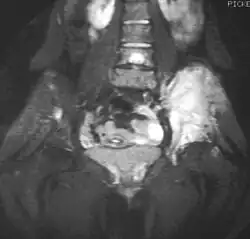

A ressonância magnética deve ser usada rotineiramente para avaliação dos tumores malignos. Ela irá mostrar a extensão no osso e tecido mole e relacionar o tumor a outras estruturas anatômicas próximas (como vasos, por exemplo). O contraste com gadolínio não é necessário já que ele não fornece informações adicionais em comparação com estudos não contrastados. No entanto, alguns estudos atuais sugerem que uma ressonância magnética com contraste pode ajudar a determinar a quantidade de necrose no interior do tumor, ajudando a determinar a resposta ao tratamento antes da cirurgia.

A tomografia computadorizada também pode ser usada para definir a extensão extra-óssea do tumor, especialmente no crânio, coluna vertebral, costelas e pelve. Tanto a tomografia computadorizada quando a ressonância magnética podem ser usados para acompanhar a resposta à radiação e/ou à quimioterapia.